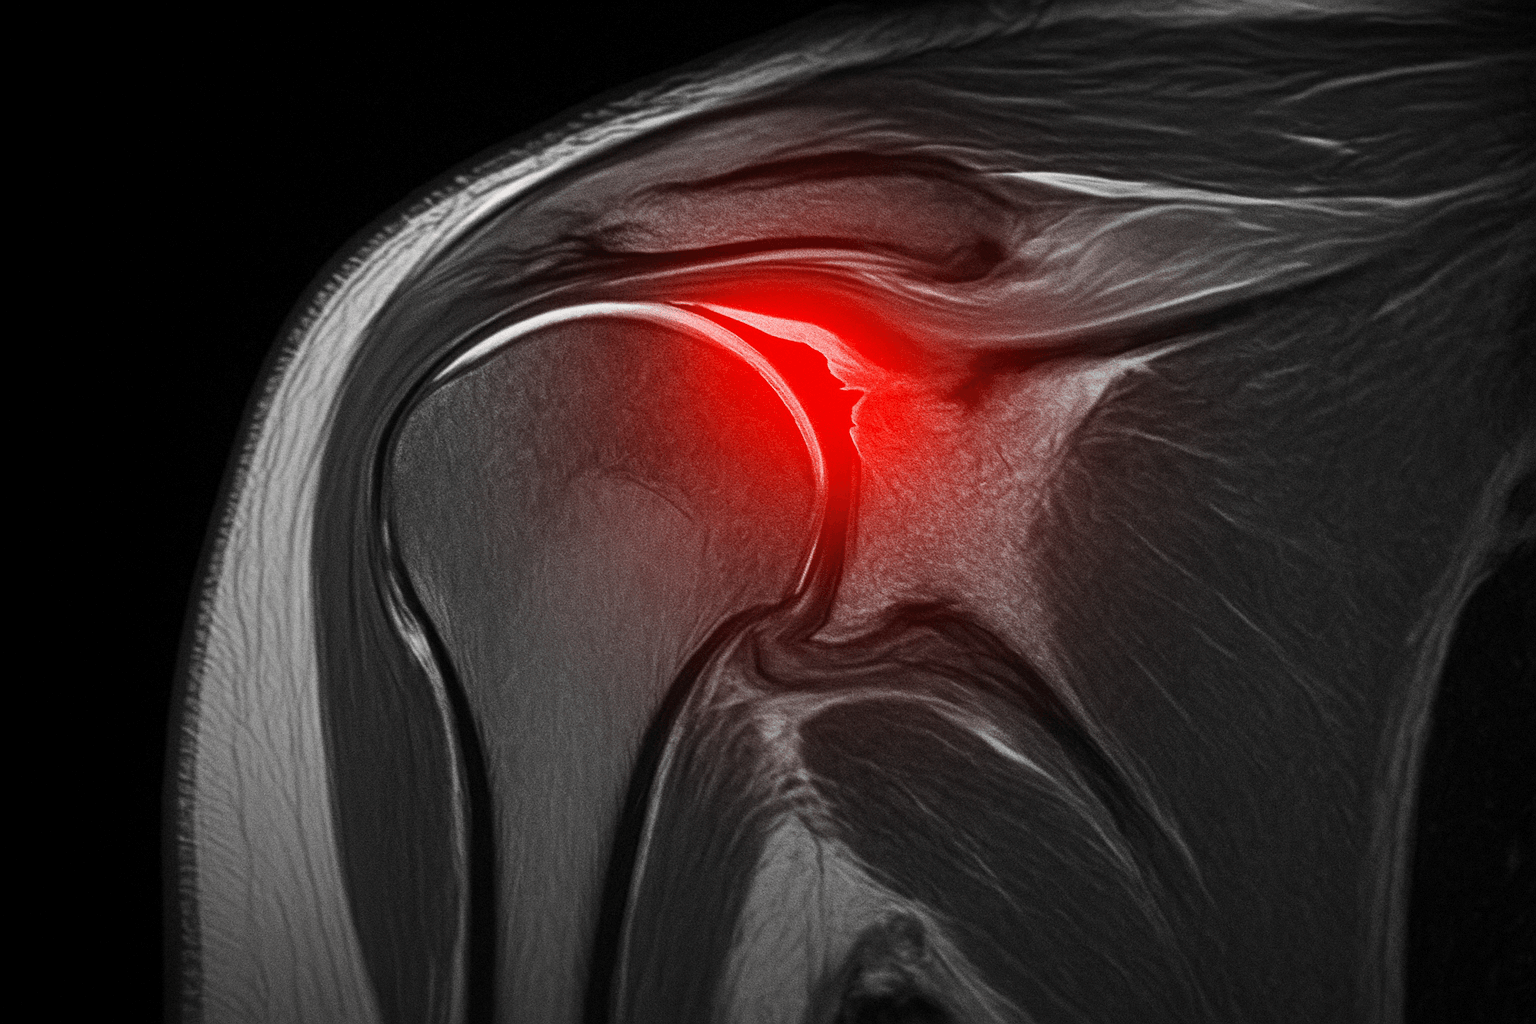

회전근개 파열, 무엇인가요? 🤔

회전근개는 어깨 관절을 안정적으로 유지하고 팔을 움직이는 데 필수적인 네 개의 힘줄(극상근, 극하근, 견갑하근, 소원근)과 그 주변 근육을 통칭하는 말입니다. 이 중요한 힘줄들이 부분적으로 손상되거나 완전히 끊어지는 상태를 회전근개 파열이라고 합니다. 주로 노화로 인한 퇴행성 변화, 반복적인 어깨 사용, 스포츠 활동 중 발생하는 외상 등이 원인이 되며, 최근에는 젊은 층에서도 발병률이 증가하는 추세입니다.

회전근개 파열 정확한 진단이 중요한 이유 💡

회전근개 파열은 흔히 '오십견'이라고 불리는 유착성 관절낭염과 증상이 유사하여 혼동하기 쉽습니다. 오십견은 어깨 관절이 굳어 모든 방향으로의 움직임에 제한과 통증이 나타나는 반면, 회전근개 파열은 특정 방향에서 통증이 더 심하고, 다른 사람이 팔을 들어주면 올라가는 등의 차이가 있습니다. 하지만 환자 스스로 정확히 구분하기는 어렵습니다. 따라서 어깨 통증이 지속된다면 전문의의 진료와 정밀 영상 검사(MRI, 초음파 등)를 통해 정확한 진단을 받는 것이 매우 중요합니다. 조기 진단은 치료 시기를 놓쳐 파열 범위가 확대되는 것을 방지하고, 더 나은 치료 결과를 기대할 수 있도록 돕습니다.